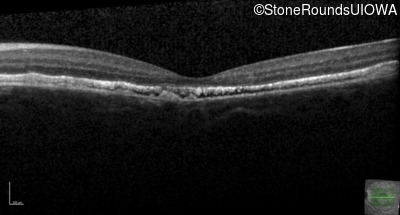

Optical Coherence Tomography - Right - 20/200 sc

Exemplar / OCT Stack

Optical Coherence Tomography - Left - 20/20 -1 sc